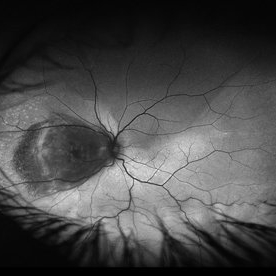

Retinitis Pigmentosa

Bilateral fundus autofluorescence images of retinitis pigmentosa.

Photographer: Olivia Rainey

Imaging device: Heidelberg Spectralis

Condition/keywords: 50 degrees, bilateral, fundus autofluorescence (FAF), hereditary retinal dystrophy, retinitis pigmentosa